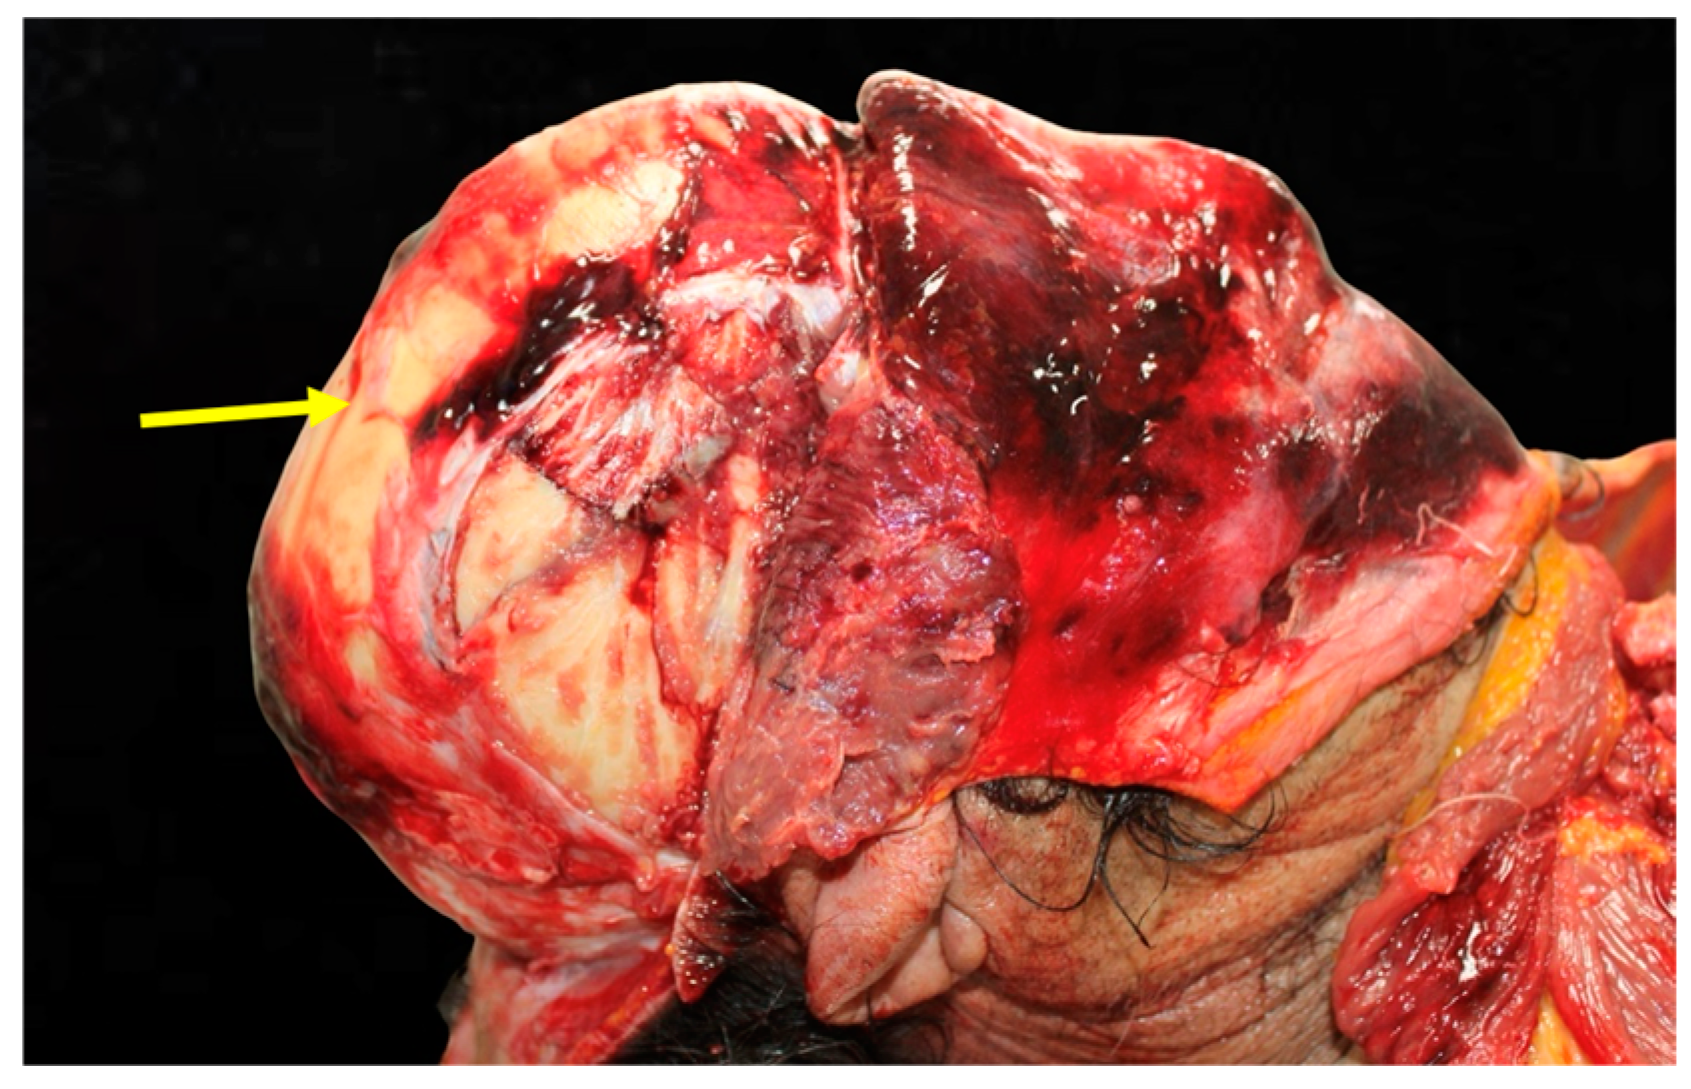

Figure 2. Cerebral hemorrhage found upon opening of the skull. This figure reveals extensive subarachnoid hemorrhage (SAH) visible upon gross examination. The bleeding pattern suggests rupture of vessels in the subarachnoid space, likely due to rapid deceleration forces during the accident.